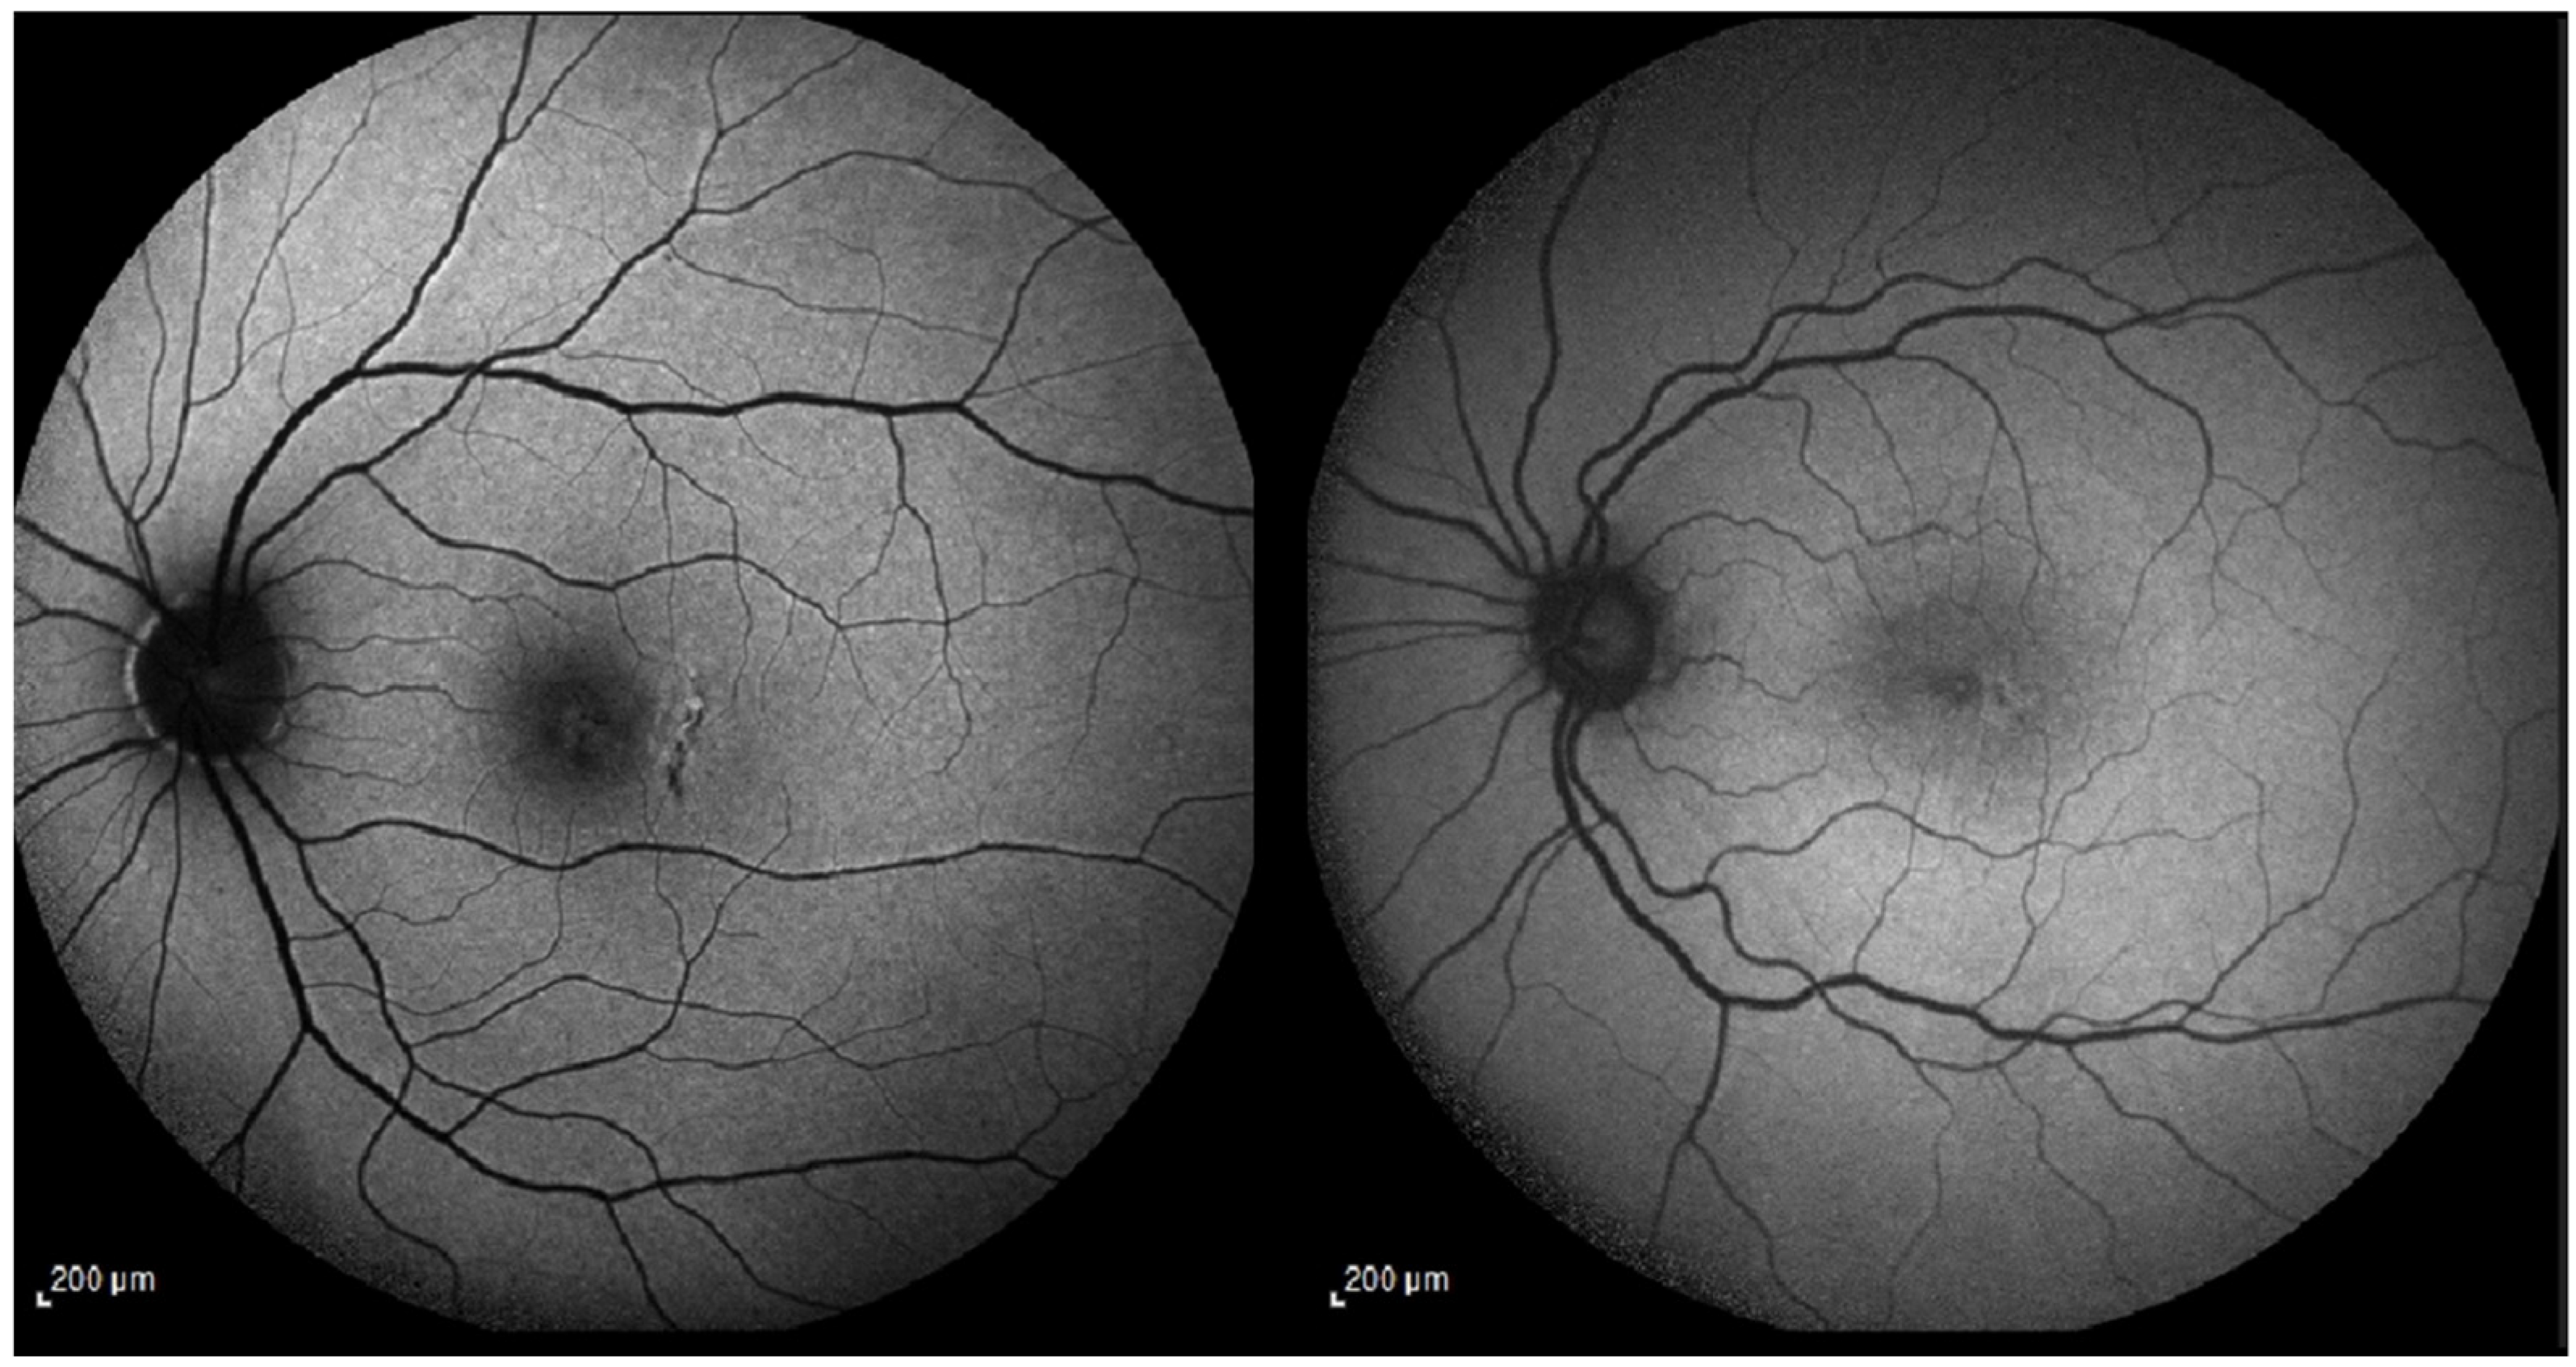

Expanded Case Study